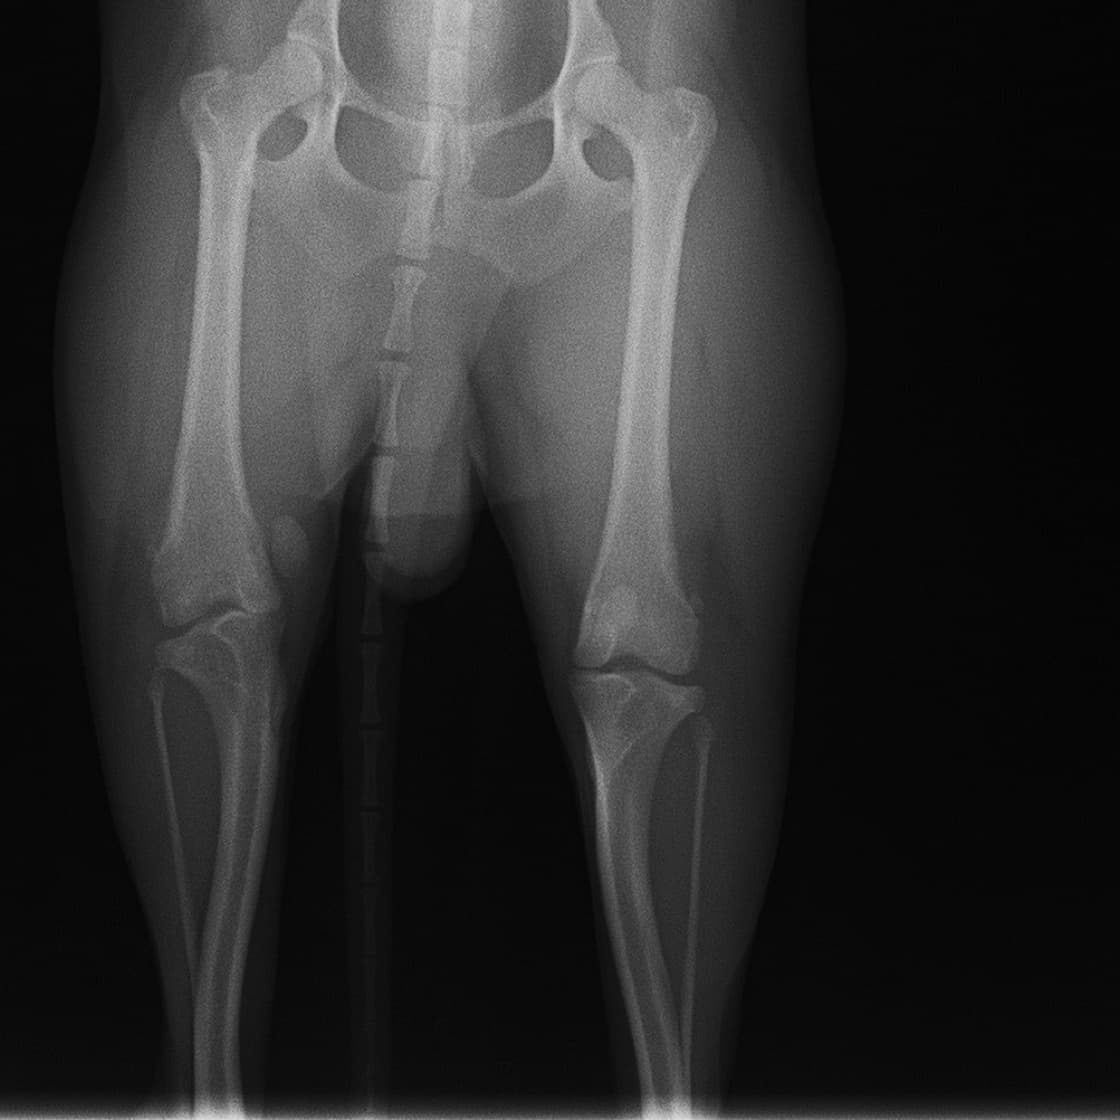

■ 症例20 ポメラニアン 8ヶ月 1.8kg

左右膝蓋骨脱臼 グレードⅢ

2ヶ月前から間欠的跛行が認められ、両膝の膝蓋骨脱臼整復術を行った。

手技は縫工筋及び内側広筋の解放、脛骨粗面の外側転位、滑車ブロック形造溝術、内外側関節包の縫縮を選択し実施した。

右側の膝蓋骨脱臼は上記手技で整復されたものの、左側はそれのみでは膝蓋骨が浮く様子が認められた。その為、PDS縫合糸にて膝蓋靱帯を1糸のみ縫合し、靱帯の縫縮を行った。

膝蓋骨脱臼は膝関節における膝蓋骨の内外側の脱臼と定義されるが、時として単純な内外の脱臼ではなく、膝蓋骨が大きく前方に浮き上がるように脱臼する場合がある。特にトイプードルやポメラニアンといった犬種に多く認められる。

内側脱臼に加えて前方への浮き上がりを矯正する為に、従来より脛骨粗面転移により膝蓋靭帯を外方と下方に引っ張り、固定する方法を選択する。膝蓋骨の前方への浮き上がりが軽度の場合は、従来法ではなく関節包の縫縮で対応していた。しかし、一部の症例で膝蓋骨の動きが悪くなり伸展機構が円滑に機能せずロボット様歩行になるケースがあった。

その為、膝蓋靭帯自体を縫縮する方法を採用した。この方法により、膝関節の伸展機構を妨げず膝蓋骨の軽度の浮きを矯正することが可能となった。

本症例の経過は良好である